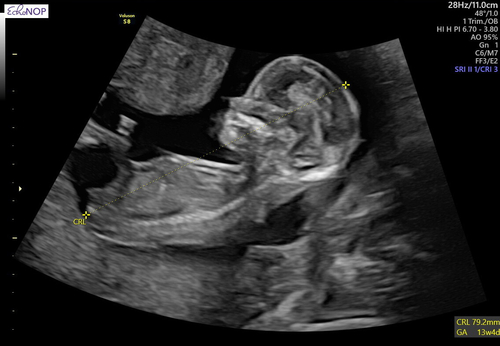

Ik heb hier nog een fotootje, maar ook vaag. Bedankt iig!🥰

Termijn?